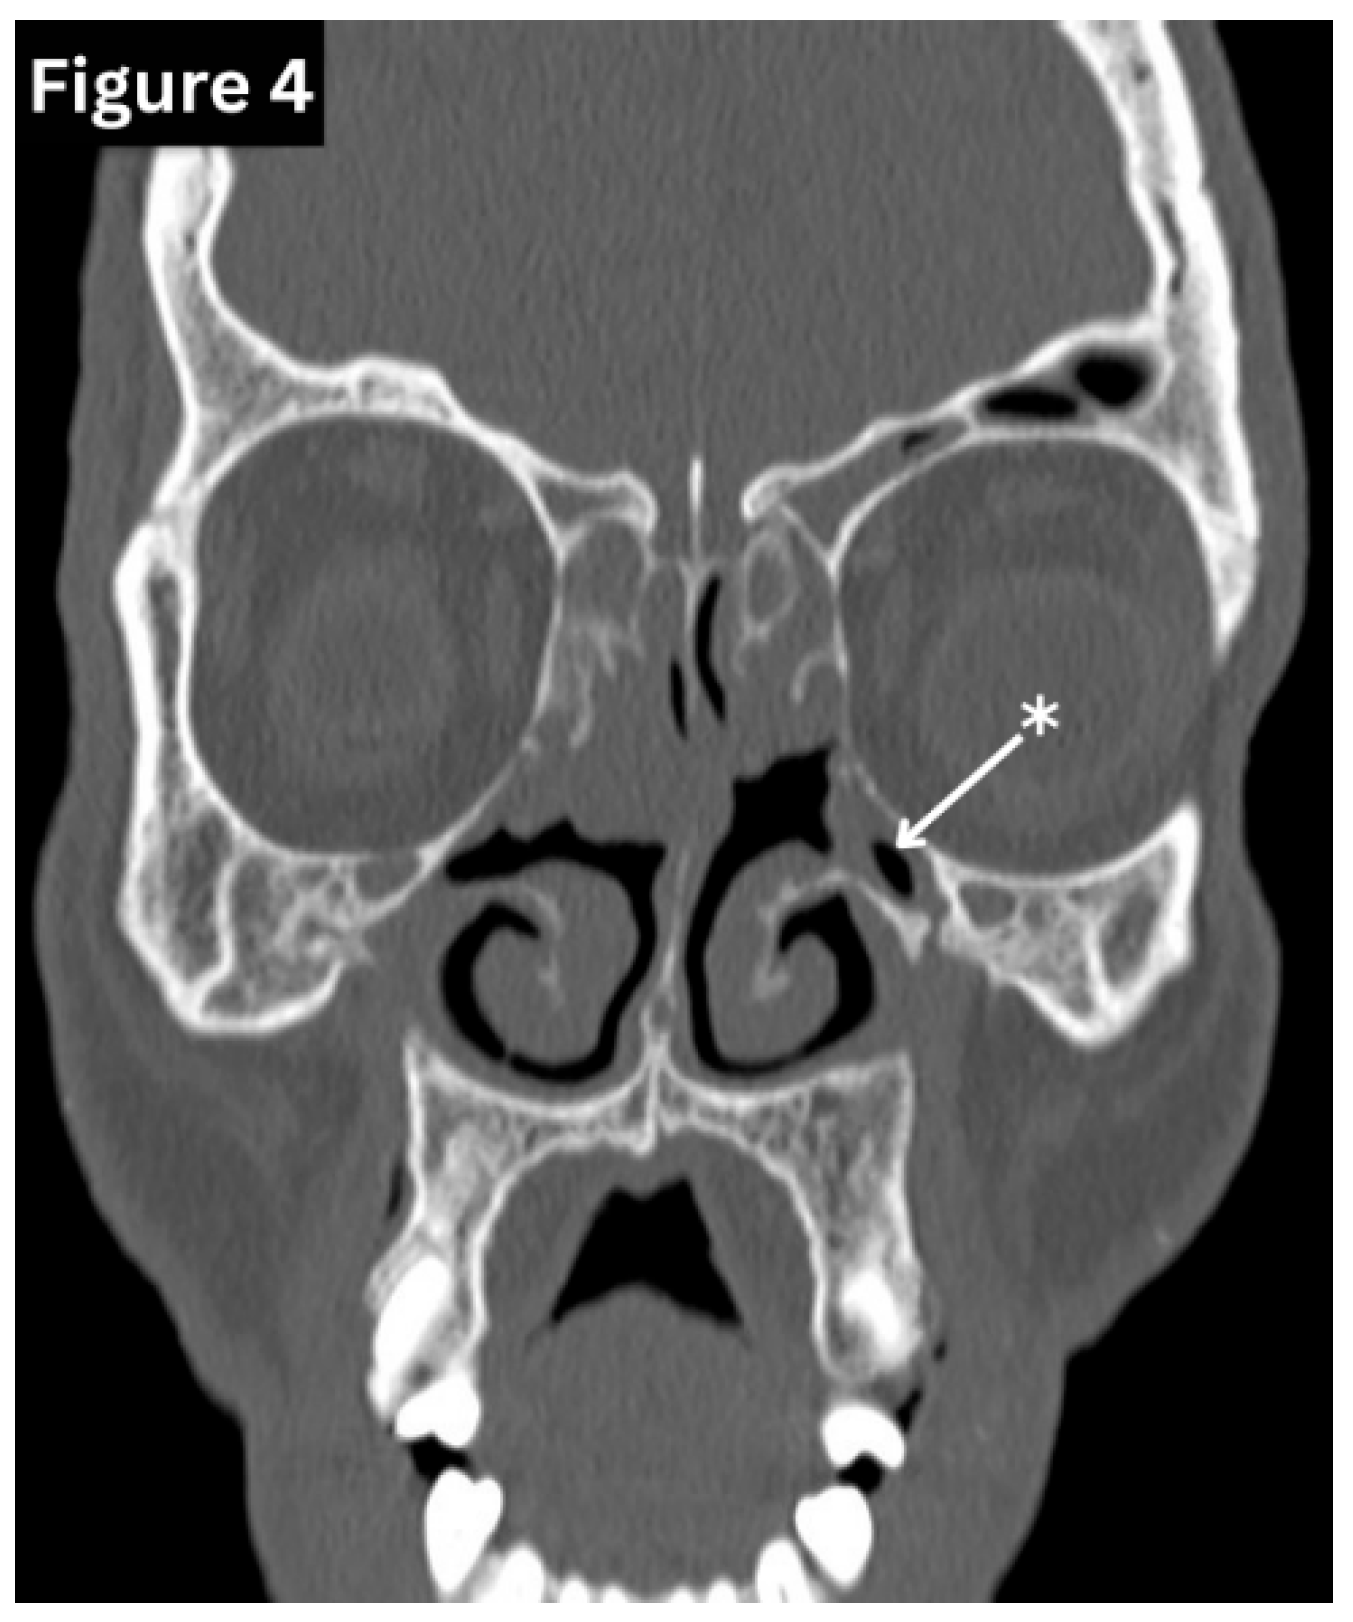

Figure 4. Coronal CT image shows hypoplastic both maxillary sinuses(arrow). (Figure 4: courtesy of Fakhry Mahmoud Ebouda, Radiopaedia.org, rID: 60030).

Anatomical variation of the paranasal sinuses is common and has important clinical and surgical implications. Variants of the maxillary sinus include internal septation, the presence of accessory ostia, and varying degrees of sinus hypoplasia. In cases of maxillary sinus hypoplasia, endoscopic intervention carries an increased risk of orbital entry, either through the lamina papyracea or the sinus floor, owing to altered anatomical relationships. (Figure 4) The frontal sinuses frequently exhibit asymmetry in size and extent and are typically separated by a midline bony septum. One or both frontal sinuses may be markedly underdeveloped or absent in certain individuals. The sphenoid sinus demonstrates wide variability of variations, ranging from partial or complete agenesis to extensive pneumatisation, including extension into the clinoid processes and adjacent pterygoid or ethmoid bones. (Figure 2) Variations in sphenoid septation, such as deviation or the presence of multiple septa, further contribute to the complexity of this region and are particularly relevant during surgical planning [9,10] (Figure 3).